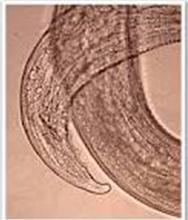

病原 大口柔線蟲(又名大口胃蟲、大口德拉西線蟲):寄生於馬胃壁的瘤腫內。白色小線蟲,雄蟲長7~10毫米,雌蟲長10~13毫米。形態特徵為咽呈漏斗狀。

馬胃蟲病蠅柔線蟲(又名蠅胃蟲):頭部鑽入胃腺內,寄生於馬胃黏膜表面。淺黃白色,雄蟲長9—16毫米,雌蟲長13~23毫米。形態特徵為咽呈圓柱狀。

小口柔線蟲(又名小口胃蟲):寄生於馬胃黏膜表面,頭部鑽入胃腺內。形態特徵與蠅柔線蟲相似,較大,雄蟲長9-22毫米,雌蟲長15~22毫米;咽亦呈圓柱狀,前端稍窄,有背齒和腹齒各一。